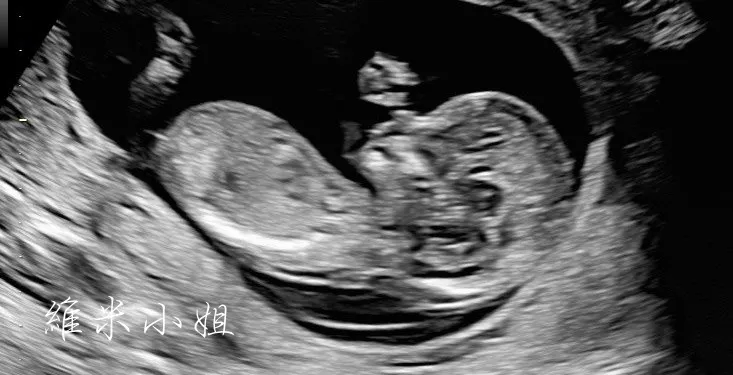

- 照超音波-測量心跳、測量胎兒大小、印超音波照

- 20-22週:高層次超音波檢查,檢查胎兒內臟器官、身體部位是否有生長異常。這在台灣不是必要項目,而且可以同時安排拍寶寶的3D照(看寶寶的五官)。

高層次超音波照